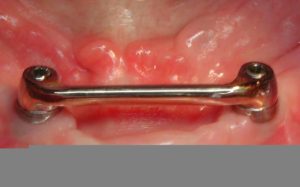

- Barre de Dolder à la mandibule

Dans cette situation, une barre de type Dolder compense plus efficacement ce porte à faux, le profil ovoïde de cette barre s’opposant plus efficacement à la bascule antérieure :

Il est donc préférable dans ces situations de concevoir une barre : la barre est orientée au laboratoire selon un axe d’insertion prothétique adapté, en l’occurence légèrement vers l’avant :

Le patient est alors beaucoup plus à l’aise pour insérer et désinsérer sa prothèse et les risques de complications mécaniques sont nettement diminués